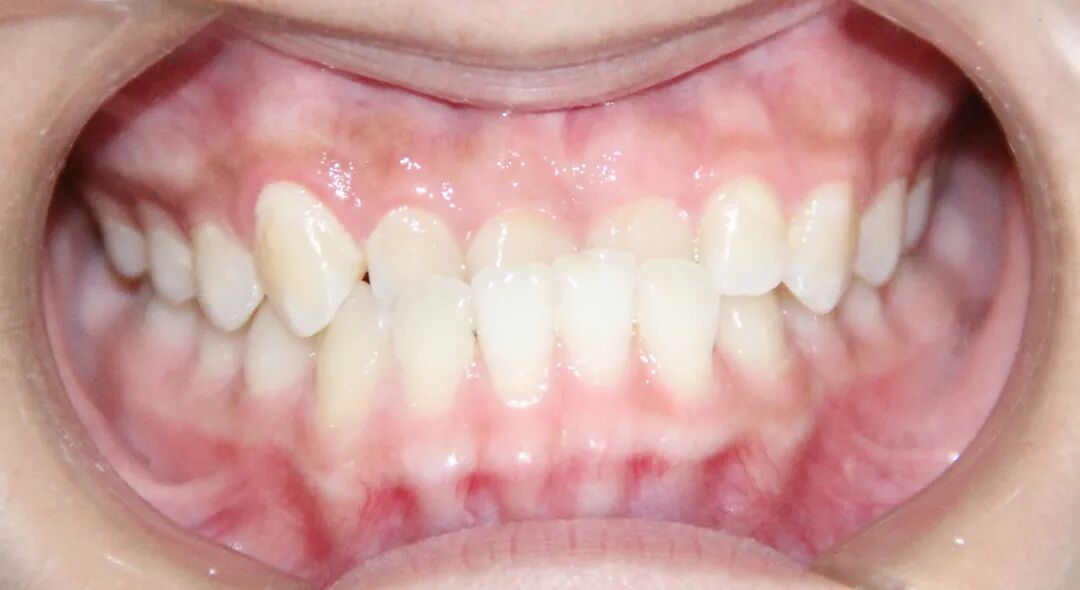

病例3

治疗前

治疗后